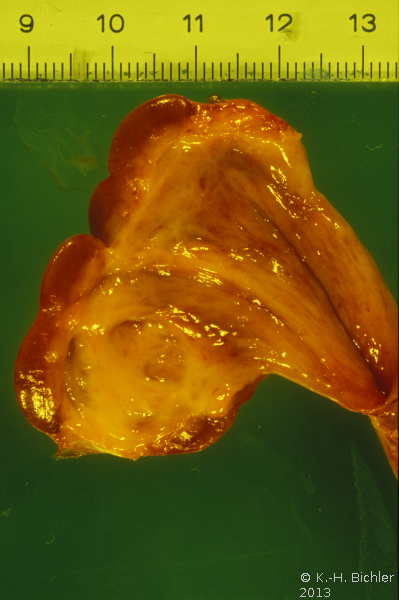

Bei einem ein Jahre alten Kind fanden sich rezidivierende, fieberhafte Harnwegsinfekte. Die Diagnostik ergab einen dysplastischen oberen Anteil der rechten Niere. Die Abbildung zeigt den entfernten dysplastichen Nierenanteil mit dem zugehörigen Harnleiter, der in eine Ureterozele mündet (Abbildung 9).